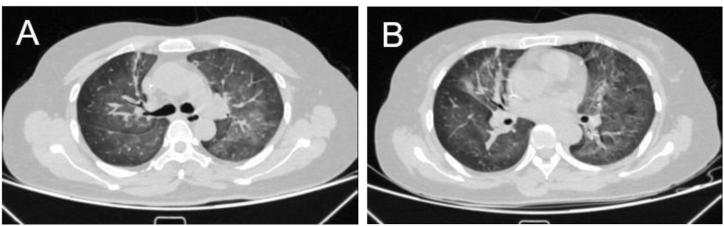

We hereby reported a case of a 52-year-old woman with breast cancer who developed acute pneumonia during neoadjuvant chemotherapy. Her serologic workup revealed a low CD4 count and positive anti-EBV antibodies. Chest computed tomography (CT) shows multiple patchy ground-glass shadows in the bilateral lung. Microscopic examination of stained sputum and bronchoalveolar lavage fluid (BALF) smear specimens did not find any pathogens. Metagenomic next-generation sequencing (mNGS) of BALF indicated a large number of EBV reads, allowing to confirm the diagnosis of EBV induced pneumonitis. The patient was then treated with ganciclovir with subsequent dramatic clinical and radiological improvement.

我们在此报告一例52岁乳腺癌女性患者,在新辅助化疗期间发生急性肺炎。她的血清学检查显示CD4计数低且抗EBV抗体呈阳性。胸部计算机断层扫描(CT)显示双侧肺有多个斑片状磨玻璃影。对染色痰液和支气管肺泡灌洗(BALF)液涂片标本进行显微镜检查未发现任何病原体。BALF的宏基因组下一代测序(mNGS)显示有大量EBV读数,从而确诊为EBV诱发的肺炎。随后患者接受更昔洛韦治疗,临床和影像学症状显著改善。